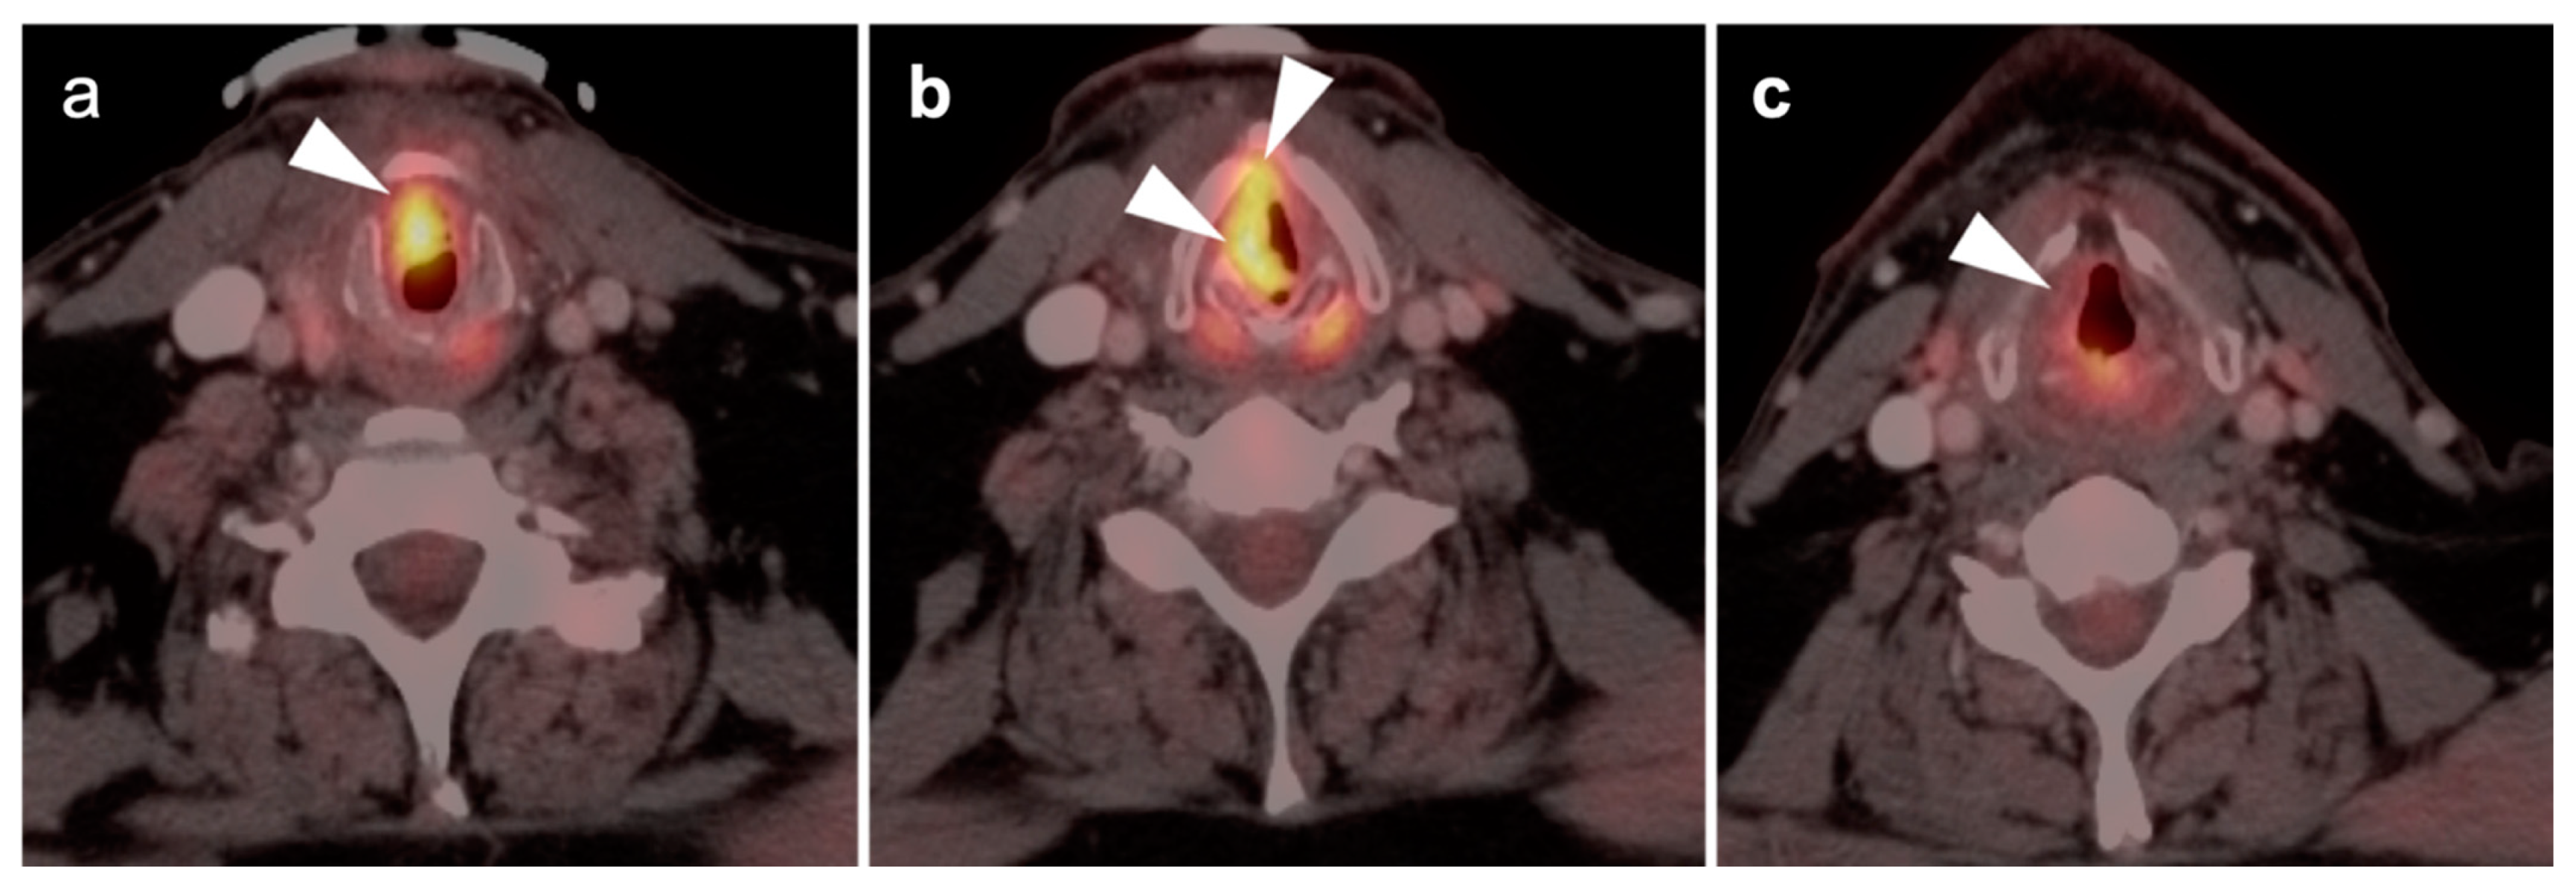

2.2. Squamous Cell Carcinoma of the Head and Neck (SCCHN)

- Laryngeal squamous cell carcinoma

- a.

- Supraglottic larynx

- b.

- Glottic larynx

- c.

- Subglottic larynx